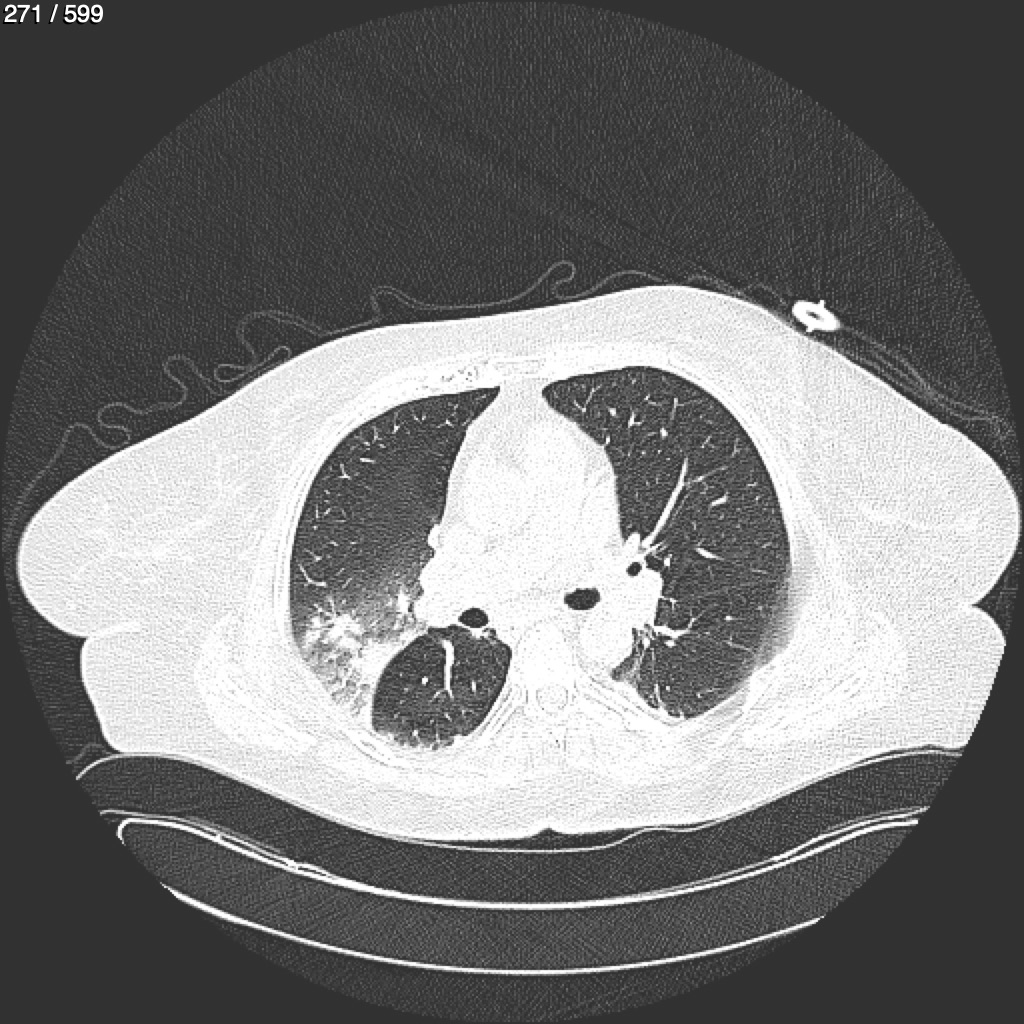

Home G​l​o​r​i​a​ ​G​l​a​d​y​s​ ​B​e​a​s​l​e​y​ ​-​ ​T​ó​r​a​x​ ​T​o​r​a​x​_​S​i​m​p​l​e​ ​(​A​d​u​l​t​o​)